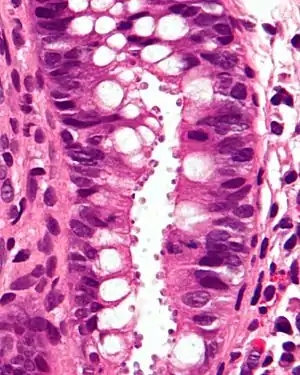

| Micrograph showing cryptosporidiosis. The cryptosporidium are the small, round bodies in apical vacuoles on the surface of the epithelium. H&E stain. Colonic biopsy. | |

Other staining techniques include acid-fast staining,[26] which will stain the oocysts red.[25] One type of acid-fast stain is the Kinyoun stain.[21] Giemsa staining can also be performed.[22] Part of the small intestine can be stained with hematoxylin and eosin (H & E), which will show oocysts attached to the epithelial cells.[25]